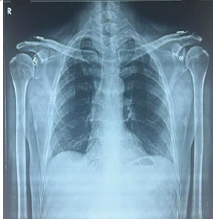

Breaking the Mold: Bilateral Lateral End Clavicle Fractures Treated with Dog Bone Button Fixation – A Rare Case

Nitesh Kumar Rathi , D Raja Sujith Kumar , J Benjamin Vinodh , Naveen Sathyaseelan , Arun Vignesh ,

………………………………p.164-168